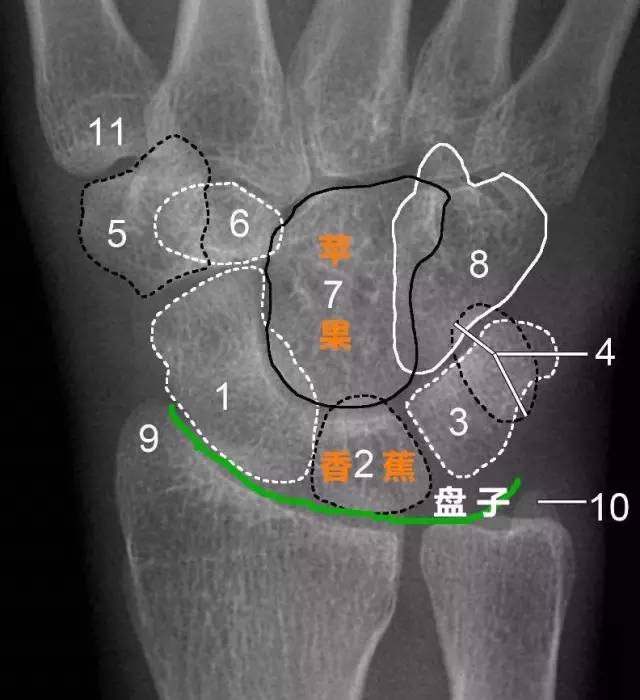

有人提出这样一种观点:我们可以把月骨看做是香蕉,把头状骨看做是苹果,香蕉下面的桡骨关节面是盘子,盘子上面有香蕉,香蕉上放个苹果,苹果被咬了一口,在前面 是三角骨骨折,香蕉歪了是月骨脱位,苹果向后是月骨周围脱位。

1.舟骨 2.月骨 3.三角骨 4.豆状骨 5.大多角骨 6.小多角骨 7.头状骨 8.钩骨 9.桡骨茎突 10.尺骨茎突 11.第一掌骨基部